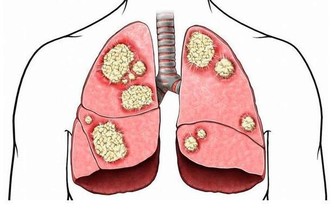

“晚上如果捂得很牢,有時候孩子的呼吸很容易壓住或者蒙住,有個醫學術語叫捂熱綜合徵,被被子捂得很牢,有的小孩子會引起高熱、脫水,最直接的包括窒息。”醫生說。

捂熱綜合徵也稱蒙被缺氧綜合徵,是嬰兒在寒冷季節中較為常見的急症之一。

主要原因包括:

①蒙被造成呼吸道受阻,引起嬰兒慢性不全性缺氧;

②過暖、大汗淋漓,造成嬰兒高滲性脫水。

捂熱綜合徵臨床表現以神經系統症狀為主、嚴重者並發呼吸衰竭、腦水腫、休克等多髒器功能衰竭等一系列的臨床症狀。嬰兒捂熱綜合徵患兒病死率高、後遺症嚴重。